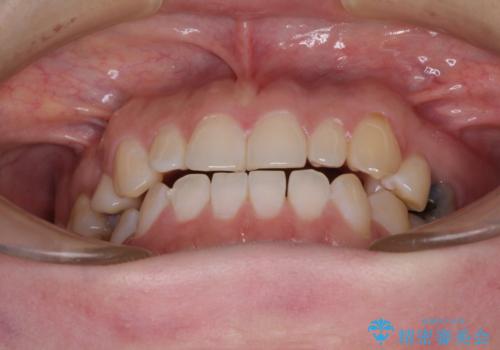

隙間の空いた歯列とボロボロの乳歯 インプラント治療と矯正治療

- 隙間の多い歯列や傾斜した奥歯、むし歯の酷い残存乳歯を気にして来院された患者様です。

歯列はワイヤー矯正にて改善することとしましたが、上下歯列にも隙間があったので、舌の突出癖を改善するトレーニングを徹底的に行うこととしました。

傾斜した下顎の奥歯は、矯正治療にてまずは歯軸を改善させ、隙間が閉じられるようであればそのままに、閉じられないようであればインプラント治療を行うこととしました。

上顎のむし歯の酷い残存乳歯は抜歯をし、矯正治療の途中でインプラントを埋入、矯正治療後に補綴治療を行うこととしました。